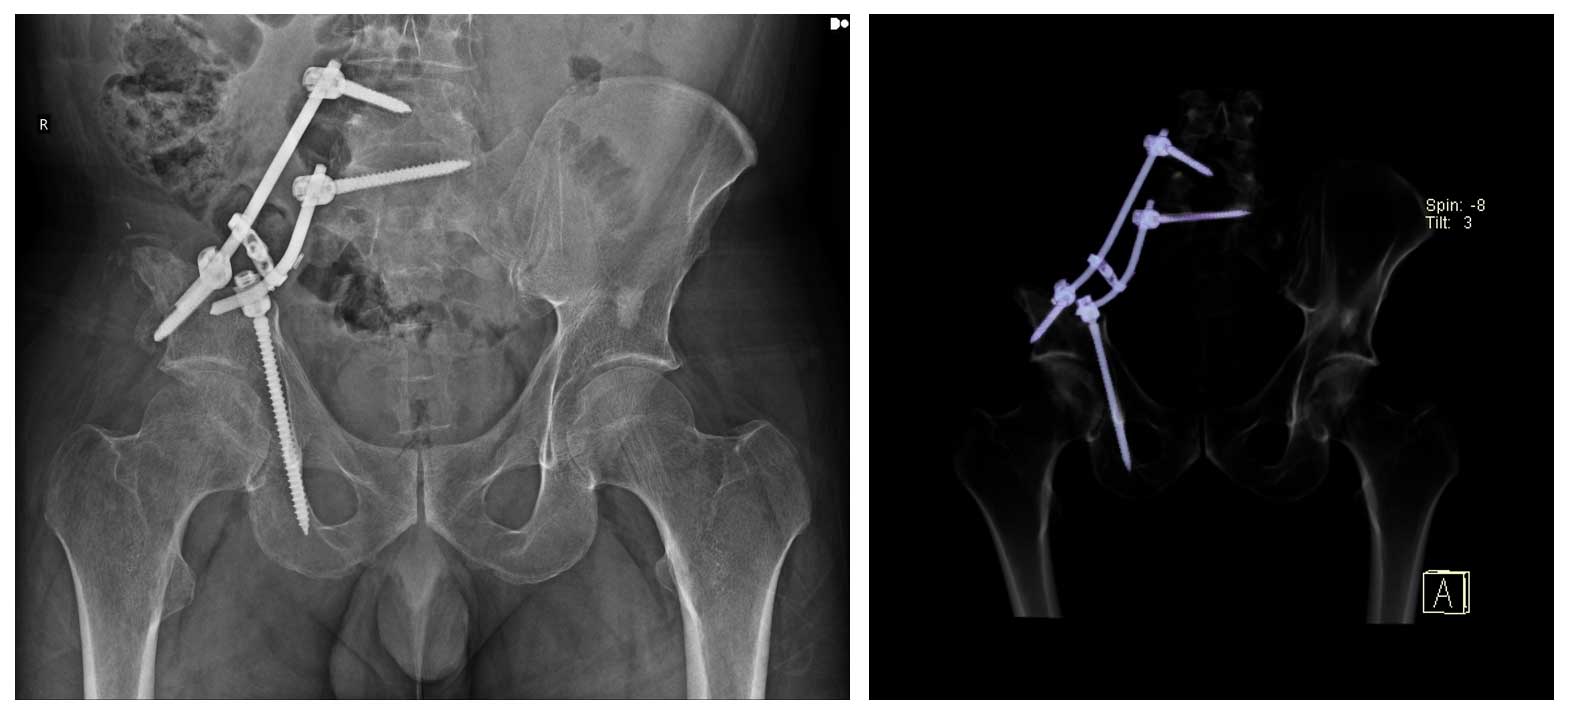

Ameliyat Sonrası: Sakroiliak rezeksiyon sonrası rod ve vidalar ile yapılan fiksasyon görülmekte.